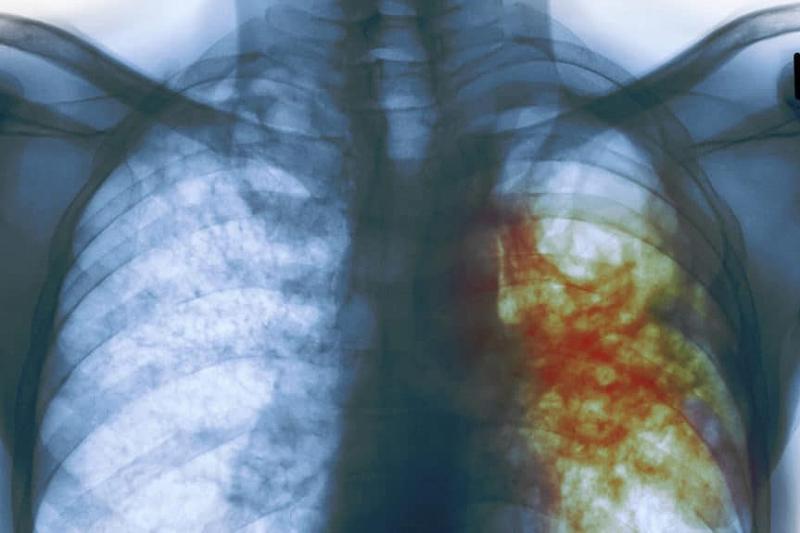

Туберкулёз - бактериальное заболевание, поражающее дыхательную систему человека, вызываемое палочкой Коха. Является древним заболеванием, по мнению ученых первые случаи заражения животных относятся к 245 миллионам лет назад. Является крайне опасным заболеванием, которое часто приводит к летальному исходу при позднем обращении за медицинской помощью. Не редки случаи, когда туберкулёз протекает без клинических проявлений (бессимптомно) долгое время, обычно при этом даёт знать о себе только на последних стадиях. Но так же имеются и клинические проявления: общее недомогание организма, температура до 38°, потеря веса, чрезмерная потливость, кашель с мокротой, хрипы, "плохие" каловые массы. На последних стадиях - рвота с кровью вместе с тканями лёгких и скопленной в лёгких жидкостью. Распространяется палочка Коха в основном воздушно-капельным путём от заболевшего к заболевшему, но может и проходить через стенки кишечника при попадании с заражённой пищей. После попадания в лёгкие медленно размножаются, что позволяет им не вызывать иммунных реакций организма долгое время. Способ лечения туберкулёза - химиотерапия противотуберкулёзными препаратами. Этих препаратов довольно много (большинство из них - антибиотики), и все они применяются практически одновременно в ходе комплексной терапии. Это связано с тем, что палочка Коха малоуязвима к антибиотикам, и при применении только одного лекарственного средства результата не будет. Способы профилактики - вакцинация БЦЖ в детском возрасте; туберкулинодиагностика - проба Манту, которая позволяет определить наличие туберкулёза у ребёнка до 15 лет; после 15 лет проводится флюорография, надёжный рентгенографический метод.